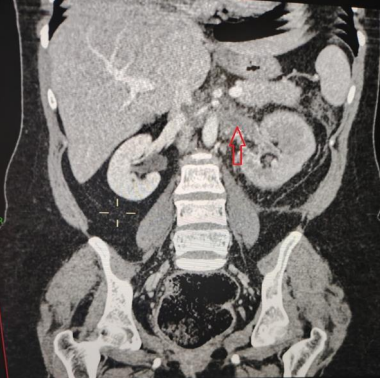

Laboratory exams revealed elevated white blood cell (WBC) count (12000 cells/mm3) with neutrophilia and (20-25 WBC in high power field) in urine examination. Other inflammatory markers like c-reactive protein (CRP) and erythrocyte sedimentation rate were also high. The initial differential diagnosis was cystitis or pyelonephritis. Abdominal ultrasound showed an enlarged left kidney, no hydronephrosis and no stones. A urine sample was sent for culture and sensitivity. The patient was admitted, and antibiotics and painkillers were initiated. An abdominal and pelvic computed tomography (CT) scan was arranged to be done the next day. CT scan with contrast showed left OVT (Figure 1, Figure 2) extending to the left renal vein (Figure 3) and inferior vena cava. Thus, she was started on anticoagulants. Urine culture was positive for Escherichia coli (ESPLs). She received low molecular weight heparin (LMWH) and shifted to warfarin. The patient was discharged home after 1 week on warfarin & oral antibiotics. A follow-up CT scan after 3 months, revealed the resolution of the clot.

Figure 3: Coronal view, contrast-enhanced CT scan demonstrates distended thrombosed left renal vein (red arrow)